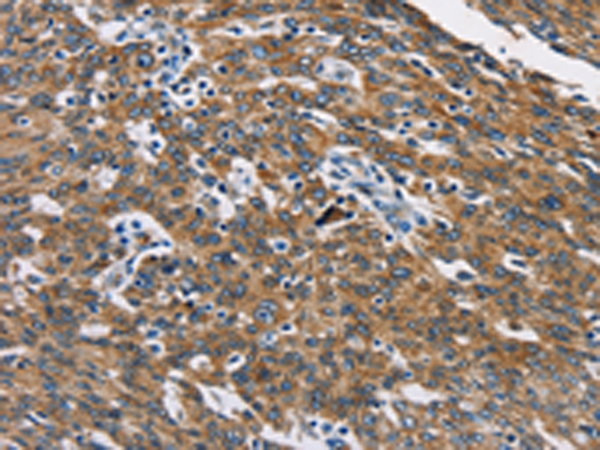

分类: 科研抗体货号: P08130别名: BTLA1; CD272应用: WB,IHC反应种属: Human